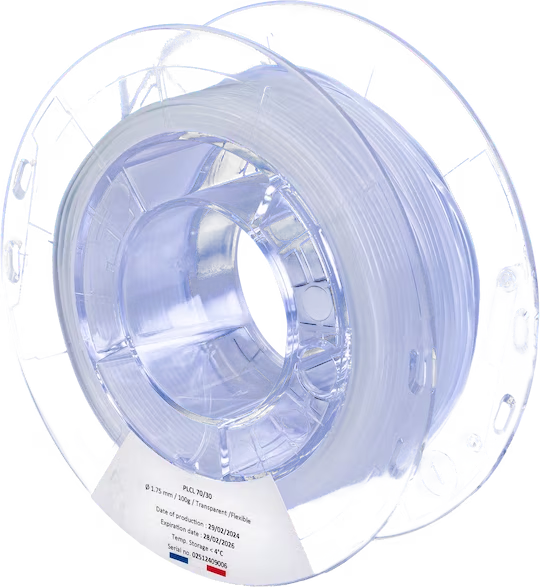

Filament copolymère de grade médical

POLY-CAPROLACTISSE 70/30

Le POLY-CAPROLACTISSE 70/30, est un copolymère d’acide poly(lactique-co-caprolactone) [PLCL] de grade médical composé d’Acide lactique (70%) et de Caprolactone (30%) de haute qualité.

Ce filament transparent est implantable et résorbable entre 12 à 24 mois et à un aspect souple.

Livré en bobine de 1.75 ou 2.85mm de diamètre pesant 100 ou 200g.

Plage de prix : € 1,300.00 à € 2,600.00

Le PLA/PCL 70 :30 ou POLY(L-LACTIDE-CO-Ε-CAPROLACTONE) 70:30 est un thermoplastique semi-cristallin, semi transparent et possède un aspect légèrement blanc. Il se résorbe entre 12 à 24 mois une fois implanté. Bien que cristallin le polymère à une température de transition vitreuse proche de la température ambiante, ce qui lui garantit une grande souplesse. Ainsi cette matière est généralement utilisée pour faire des renforts pariétaux, des guides de reconstruction nerveuse.

Informations générales

Type de consommable : Filament

Matière : POLY(L-LACTIDE-CO-E-CAPROLACTONE) PLCL

Couleur : Transparent

Aspect : Souple

Diamètre : 1,75 mm – 2,85 mm

Poids : 100g – 200g

Fabrication : France

Avantages

Biorésorbable

Biocompatible

Souple

Flexible